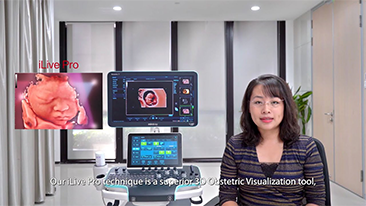

Supportata dalla piattaforma avanzata ZST+, la gamma completa di soluzioni smart di Nuewa ├© progettata appositamente per migliorare la salute della donna durante il periodo pre-gravidanza, la gravidanza e il recupero post-parto, per fornire diagnosi complete ed efficaci e per rispondere a sfide cliniche sempre pi├╣ impegnative.